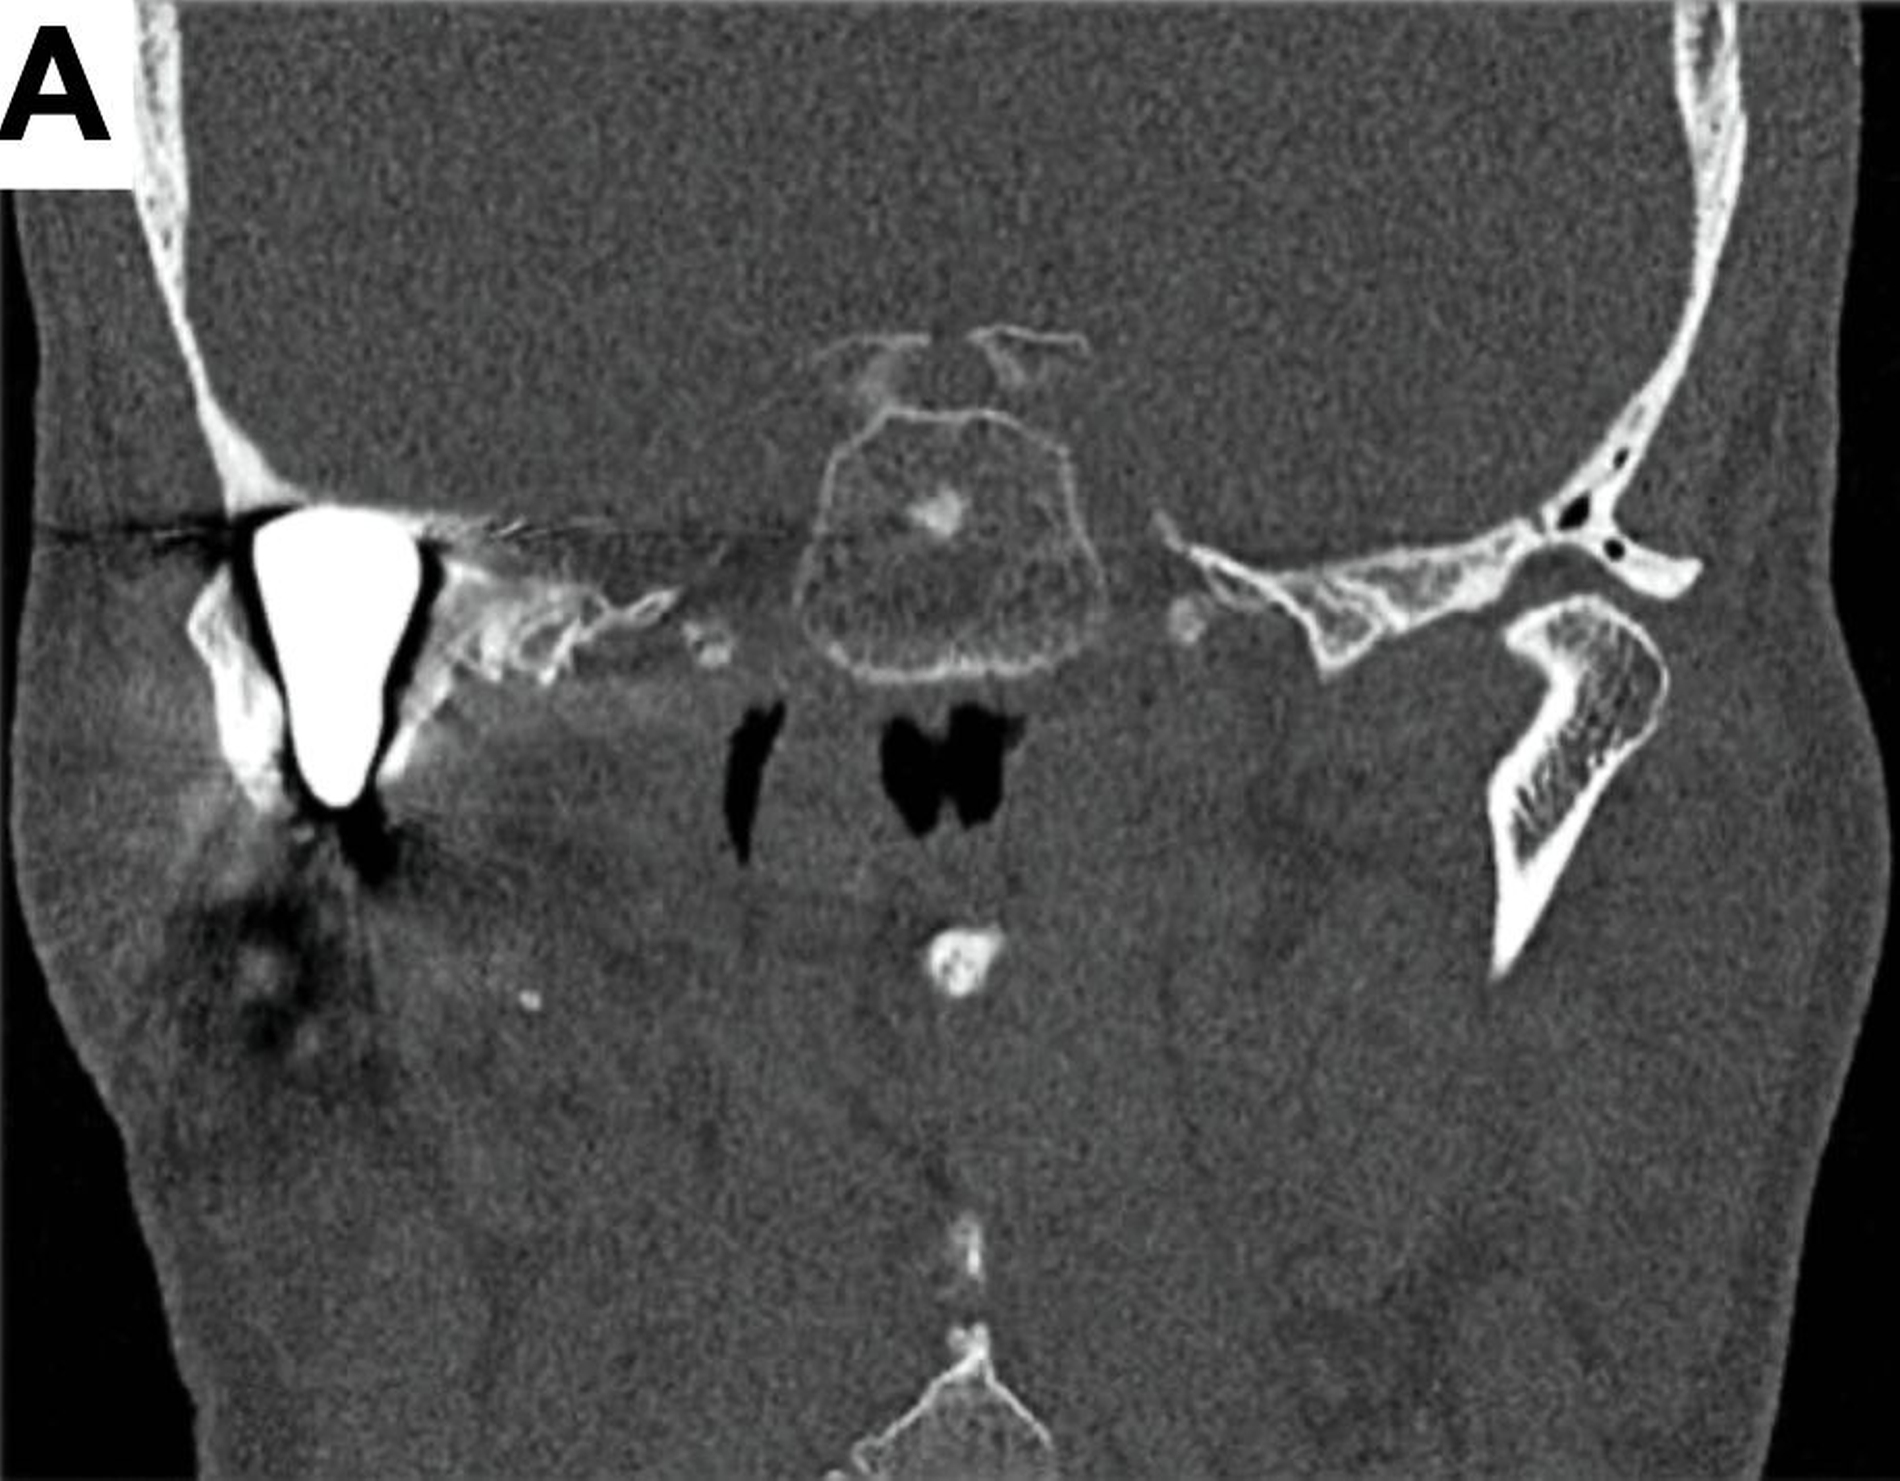

Bei der computertomografischen Untersuchung, die während der Patientenvorstellung durchgeführt wurde, wurde der totale Ersatz des rechten Kondylus durch die bereits beschriebene Endoprothese festgestellt, jedoch ohne Ersatz der Fossa mandibulae, was einem partiellen Kiefergelenkersatz entsprach. Das in situ befindliche Prothesenwerkstück hatte bereits zu einer nahezu vollständigen Erosion der mittleren Schädelbasis geführt (Abbildung 1).